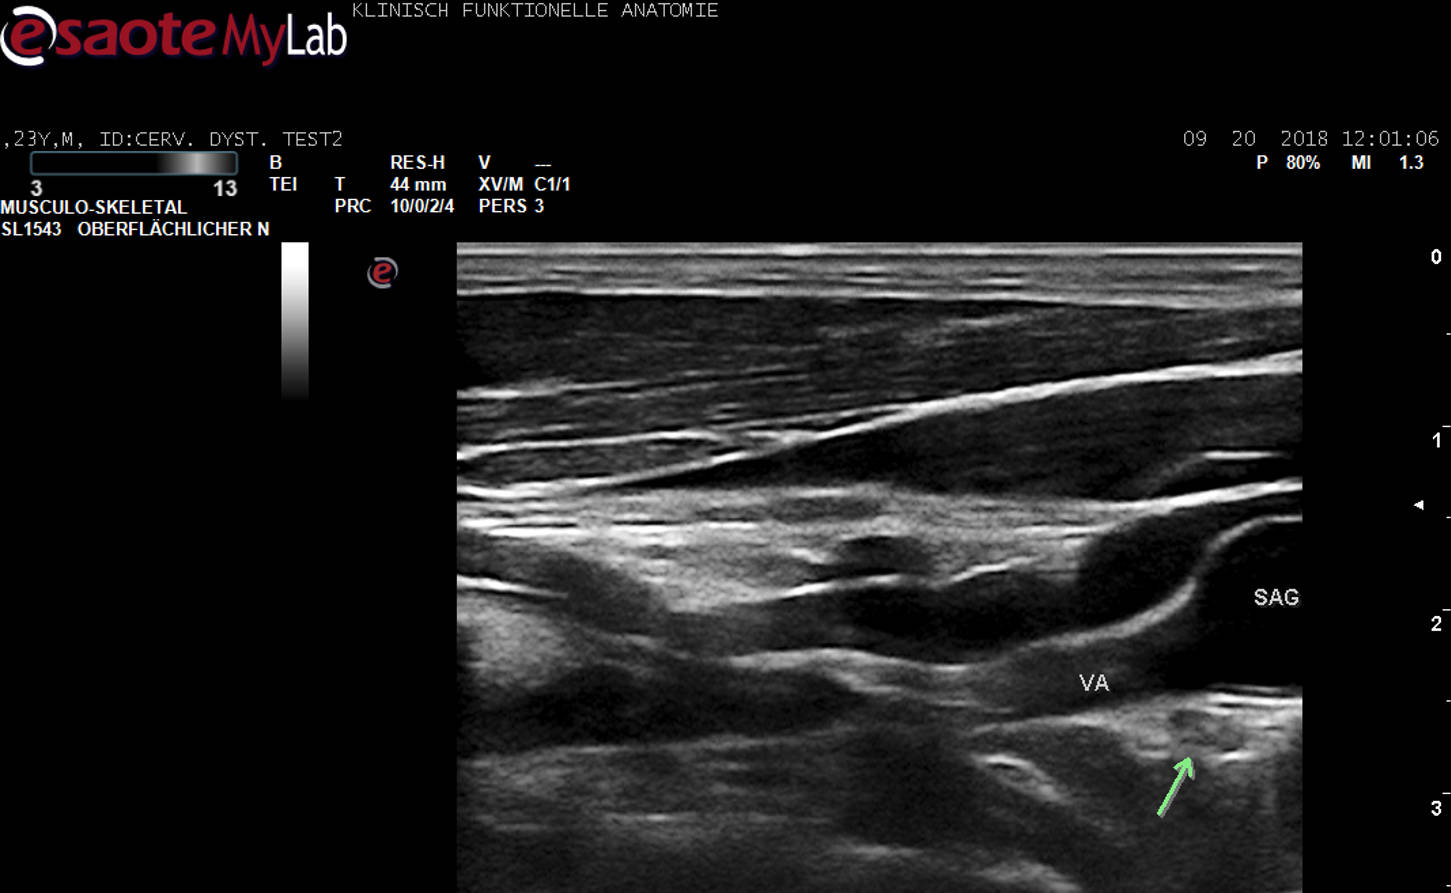

Beispiel detaillierte Sono-Anatomie und Topographie am Lebenden.

Weltweit erste US-Darstellung des Ganglion stellatum (grüner Pfeil) in unmittelbarer Nachbarschaft zur A. vertebralis (VA).